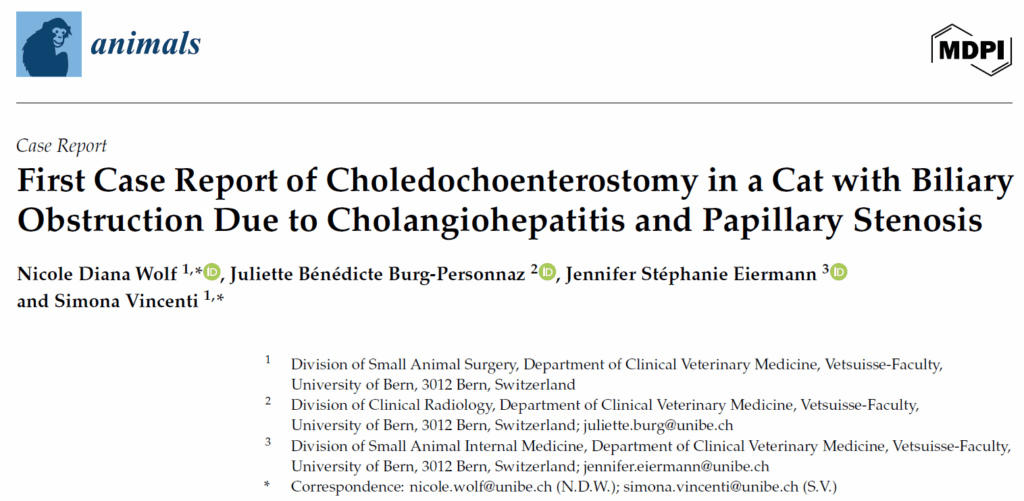

超声显示胆囊和胆总管显著扩张(下图)。两者均含有大量重力依赖性回声物质,伴有高回声焦点和斑点,以及非重力依赖性无回声物质。胆囊和胆总管的壁中度增厚且呈高回声,并表现出轻度不规则。

↑ (A) 胆囊(*)显著扩张,(B) 胆总管(+)显著扩张,管腔变细(箭头)和胰管轻度扩张(-),(C) 十二指肠乳头(椭圆形)进入十二指肠(<)。

胆总管在靠近十二指肠乳头处出现管腔突然变细(上图B),而乳头本身在超声检查中显示正常。肝内胆管轻度扩张。胰管在其最远端轻度扩张(上图B)。胃部中度向右侧前腹腔移位,与相邻胆道结构的压迫效应一致。发现少量无回声腹腔积液。

这些发现与肝外胆道梗阻一致,最可能发生在十二指肠乳头处或其近端,可能是由于黏液栓、狭窄或其他梗阻原因引起的。反应性腹腔积液和轻度胰管扩张可能反映了早期继发性炎症或压力相关变化。